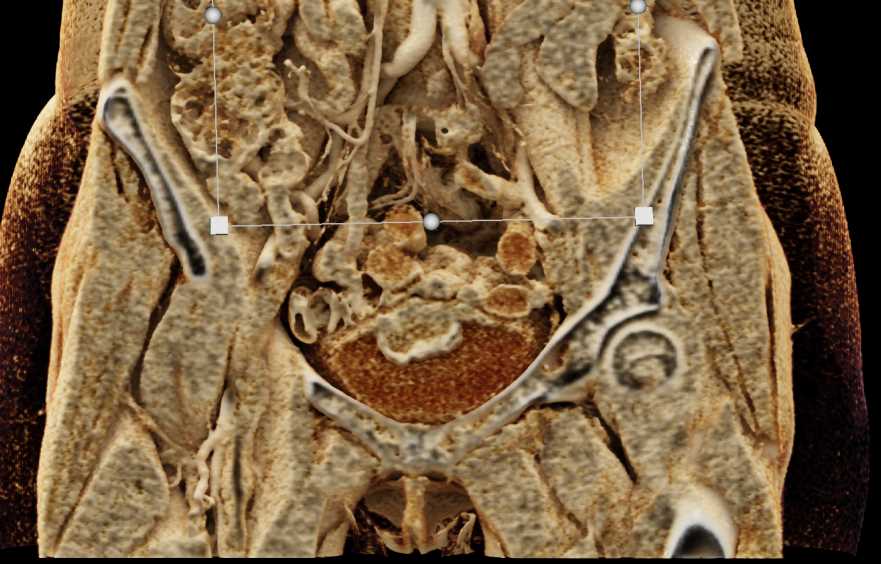

Urachal Carcinoma of the Bladder